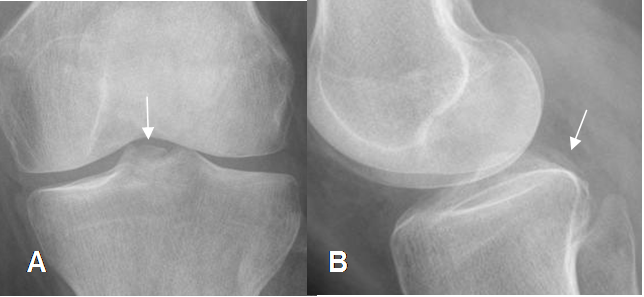

Fig 111. Avulsión del LCP.

A: Rx AP y B: Rx lateral. Presencia de fragmento óseo central y de localización posterior, por avulsión sobre la inserción del LCP.